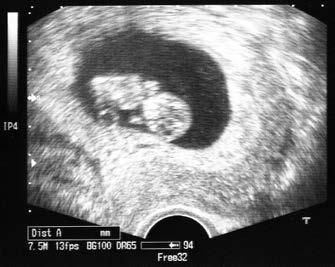

Vývoj plodu, 10. týden těhotenství (ultrazvukový snímek)

Definitivní jistotu o správném uložení v děloze a o tom, že zárodek je živý, nám dává ultrazvukové vyšetření, které bývá v časném těhotenství kvůli přesnosti obvykle prováděno vaginální sondou. Uložení těhotenství v děloze jsme schopni rozlišit již v 5. týdnu těhotenství (tedy pět týdnů od prvního dne posledních měsíčků). Že je zárodek živý, lze pak poznat zhruba o týden později, kdy je ultrazvukem vidět pulzující srdce.

Vývoj zárodku je v prvním trimestru velice rychlý a bouřlivý. V 8. týdnu je délka zárodku 22–27 milimetrů, má již tvar lidského těla, hlava je v poměru k ostatnímu tělu výrazně větší, jsou vyvinuty rysy obličeje, končetiny mají vyvinuté prstíčky. Většina orgánů je již na svých místech, nejsou však ještě zcela plně vyvinuty, především pokud jde o jejich funkci.

Vývoj plodu, 12. týden těhotenství